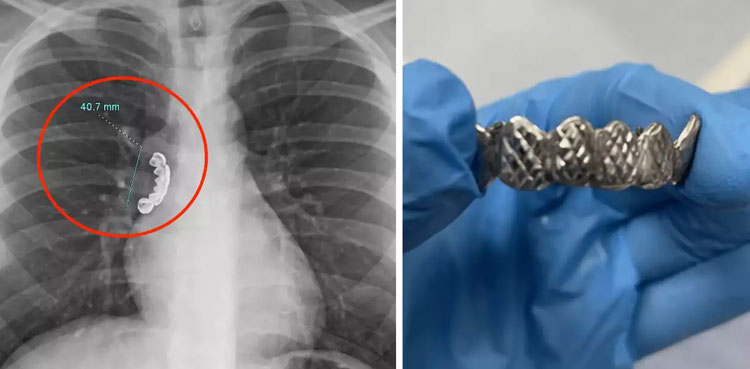

Upon arriving at the hospital, the patient experienced severe coughing and wheezing, nearly choking on the lodged dentures. An urgent X-ray examination revealed a 4.1 cm denture obstructing the airway of his lung.

To extract the dentures from the airway, doctors performed a bronchoscopy—a delicate procedure involving the insertion of a thin, illuminated tube called a bronchoscope.

A flexible bronchoscope was employed, and under direct visualization, toothed forceps were used to safely detach the dental device from the bronchial wall.